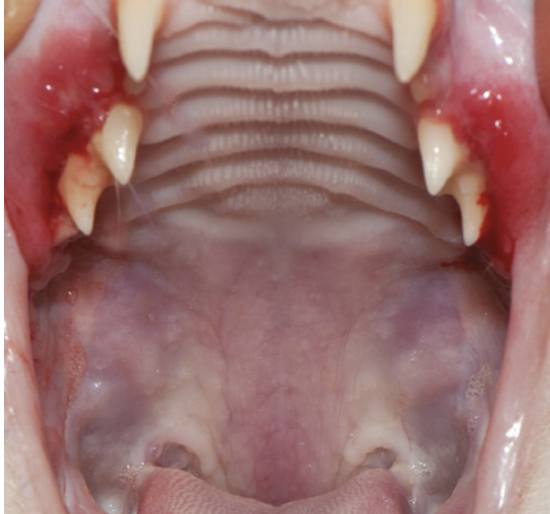

- Тип 1 характеризуется наиболее благоприятным прогнозом. Типичным примером данного типа является альвеолярный, лабиальный/буккальный мукозит или стоматит (фото 1).

- Тип 2 представляет собой каудальный мукозит, который может сопровождаться альвеолярным и лабиально-буккальным мукозитом/стоматитом или протекать изолированно (фото 2).

При осмотре выявлены (фото 3) увеличение нижнечелюстных лимфатических узлов, болезненность при осмотре полости рта, каудальный гингивостоматит с симметричными билатеральными поражениями (гингивит – воспаление десны, прилегающей к поверхности зуба), объемное образование мягкого зубного налета.

Результаты осмотра. Выявлена болезненность при пальпации ротовой полости. Обнаружены признаки каудального гингивостоматита и мукозита с симметричными билатеральными поражениями на слизистой оболочке каудальной части ротовой полости и щек, подвижные зубы, признаки пародонтита, а также значительные минерализованные и неминерализованные зубные отложения (фото 8, 9).